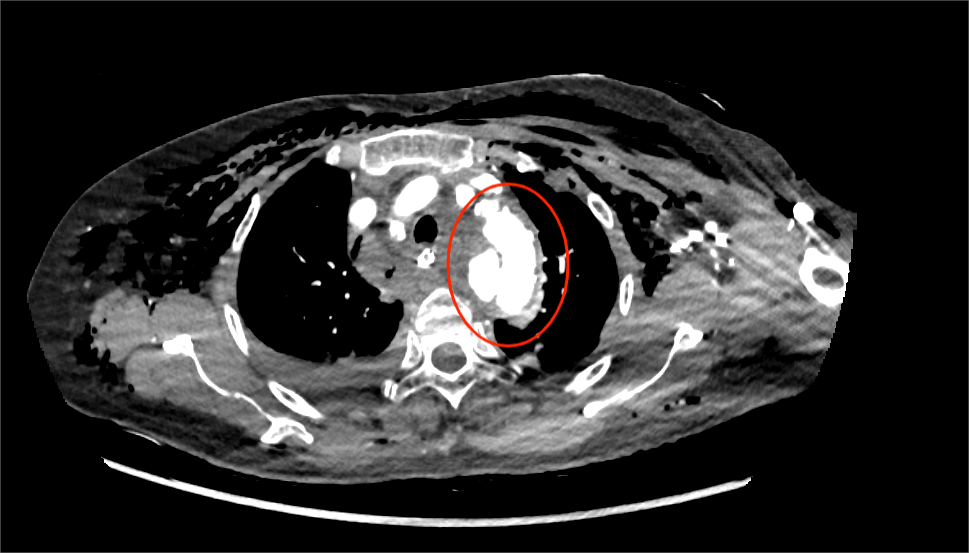

患者路女士,75岁,因车祸后出现胸部疼痛、呼吸困难,被紧急送至医院。检查发现其伤情复杂,包括多发肋骨骨折、锁骨骨折、颅骨及腰椎骨折、脑脊液漏、创伤性血气胸、应激性溃疡伴出血、创伤性休克等,后续进一步诊断为创伤性主动脉夹层(B型)。面对如此涉及多个系统、部位的重症伤情,医院立即启动多学科协作机制。

泛血管疾病管理中心在此过程中发挥了重要的协调与整合功能。中心秉承“全身血管一体考量”的理念,统筹心胸外科、心内科、神经外科、骨科、麻醉科、重症医学科等相关专科资源,为患者制定个性化、系统化的治疗方案。在控制血压、稳定生命体征的基础上,医疗团队先后为患者实施“冠状动脉造影术”、“主动脉覆膜支架腔内隔绝术”及“肋骨骨折切开复位内固定术”。术后,患者经重症监护与心胸外科病房的协同康复,病情逐步平稳,最终好转出院。